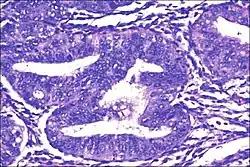

Micrograph showing simple endometrial hyperplasia, where the gland-to-stroma ratio is preserved but the glands have an irregular shape and/or are dilated. Endometrial biopsy. H&E stain.

Like other hyperplastic disorders, endometrial hyperplasia initially represents a physiological response of endometrial tissue to the growth-promoting actions of estrogen. However, the gland-forming cells of a hyperplastic endometrium may also undergo changes over time which predispose them to cancerous transformation. Several histopathology subtypes of endometrial hyperplasia are recognisable to the pathologist, with different therapeutic and prognostic implications.[4]

• Endometrial hyperplasia (simple or complex) - Irregularity and cystic expansion of glands (simple) or crowding and budding of glands (complex) without worrisome changes in the appearance of individual gland cells. In one study, 1.6% of patients diagnosed with these abnormalities eventually developed endometrial cancer.[7]